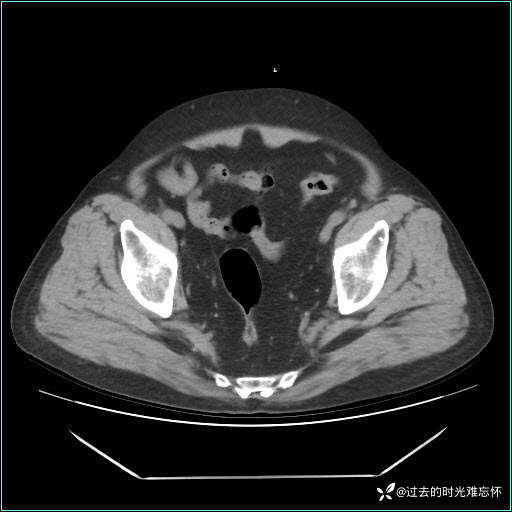

男子肚子大如孕晚期,一看腹腔竟被脂肪填满了...

患者男,71 岁,因「反复腹痛腹胀 1 月」入院。

现病史:患者 1 月前无明显诱因下出现腹痛腹胀症状,腹痛呈隐痛,当时未予以重视,后症状有所加重,常在进食辛辣刺激油腻等食物后出现腹痛,口服药物治疗症状能得到控制,病情控制一般。现为求诊治来我院,拟“腹痛”入院。病程中患者神志清楚,精神一般,无咳嗽咳痰,无恶心呕吐,近期体重无明显变化。